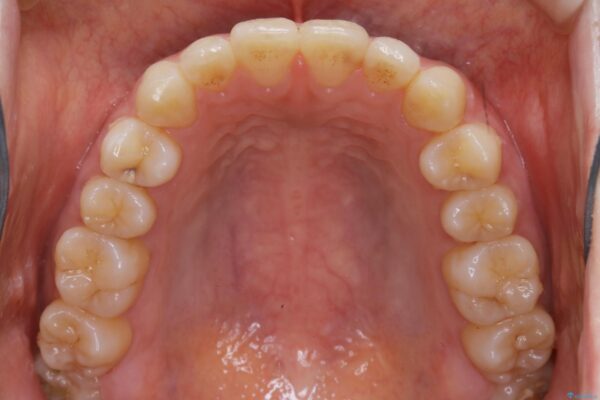

インビザラインのライトパッケージにて、歯列拡大とディスキング(IPR)をを行いスペースをつくり非抜歯で治療を行いました。

歯並びが悪くなる原因の一つに「歯列弓の狭窄」というものがあります。

奥歯や前歯が内側(舌側)に倒れ込んでしまったり、歯が生えてくる位置が内側になってしまうことにより歯並びのアーチが狭くなってしまうことを言います。

このような場合、歯並びのアーチを拡大してあげるだけでもガタつきを無くすためのスペースがかなり作れることがあります。